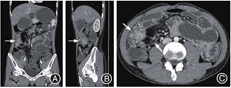

影像学检查:入院后给予禁食和静脉补液后患者腹痛缓解、肛门排气恢复,遂行全腹CT平扫加增强,显示右中下腹局部小肠肠壁水肿增厚,增强后明显充血,周围脂肪间隙浑浊伴多发渗出,见一3.5 cm × 4.1 cm的不规则软组织团块影,见图1A、1B;病变肠管周围多发扩张、迂曲血管影,见图1C;病灶近端肠管扩张,远端肠管内见多量液体。肠系膜上动脉CTA示动脉走行良好,未见充盈缺损或瘤样扩张,见图2A。